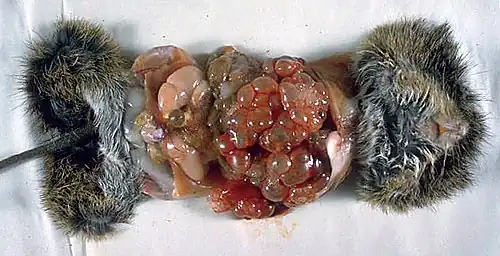

Die Larve durchdringt das Epithelgewebe der Darmwand und gelangt über die Mesenterialvenen und die Pfortader zur Leber des Zwischenwirts, sie kann aber in Ausnahmefällen auch Lunge, Herz oder Milz befallen. Innerhalb des Gewebes setzt sich die Onkosphäre fest und bildet als zweites Larvenstadium die Metazestode oder Finne, die auch als Echinococcus alveolaris[21] bezeichnet wird. Sie ist eine mit gallertartiger Masse gefüllte Blase, die gegen das sie umgebende Organ durch eine Wand aus Bindegewebe abgegrenzt ist. Wie dieser Vorgang ausgelöst und gesteuert wird, ist nicht bekannt.

Aus der Wand der Metazestode entspringen im weiteren Verlauf der Infektion durch Knospung stetig weitere Finnen; es entsteht eine Larvenstruktur, die aus einer Anhäufung blasenartig erscheinender Finnen besteht und das Wirtsgewebe infiltriert. Sie wird daher als Hydatide des alveolären (blasenartigen) Typs von der Hydatide des zystischen Typs des Hundebandwurms abgegrenzt, bei dem durch eine Knospung nach innen eine große Hydatidenblase gebildet wird. Im Rahmen der Knospung können sich Zellverbände oder einzelne Zellen der Metazestode ablösen, über die Blutbahn des Wirts andere Organe erreichen, sich dort festsetzen und weitere Befallsherde bilden.

Beim Menschen als Fehlwirt ist die Knospung der Metazestoden stark verlangsamt und es bilden sich allenfalls wenige Protoscolices. Die Metazestode wächst nach außen, und es kommt in ihrem Zentrum zu Abbauprozessen. So entsteht eine langsam zunehmende Masse aus nekrotisiertem Gewebe, das von einer relativ dünnen Schicht lebenden Parasitengewebes umhüllt ist.

Als Zwischenwirt dienen kleine Säugetiere, vor allem Wühlmäuse, die in Deutschland die häufigsten Zwischenwirte sind. Bei ihnen führt eine Infektion mit den Larven des Fuchsbandwurms innerhalb weniger Monate zu einer starken Schwächung oder zum Tod.[10]